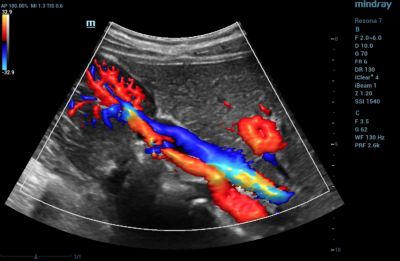

Ultra Micro Angiography (UMA)

is an innovative method of visualizing low-velocity micro-vascular flow states. UMA compensates for the limitations of traditional flow modes in detecting slow flow. It allows for visualization of the supply vessels surrounding diseased tissues, further enhancing diagnostic capabilities for lesion detection and characterization.

• Color UMA – UMA with a traditional color map overlay for improved sensitivity

• Power UMA – UMA with Power Doppler sensitivity, also available in bidirectional mode

• Subtraction UMA – UMA combined with tissue subtraction for enhanced evaluation of vessels separate from grayscale imaging